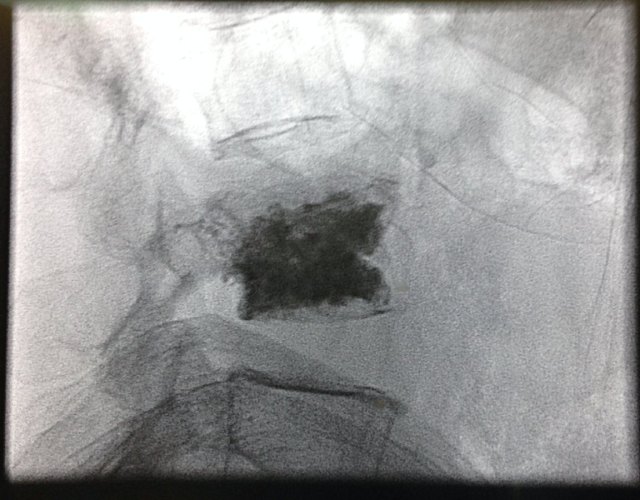

As she had multiple drug allergies and it was difficult to control her pain with oral medications, a minimally invasive procedure to inject bone cement into her fractured vertebra was suggested.

Mdm P was agreeable to this procedure and this was performed under x-ray (fluoroscopic) guidance with her being sedated by an Anaesthetist.